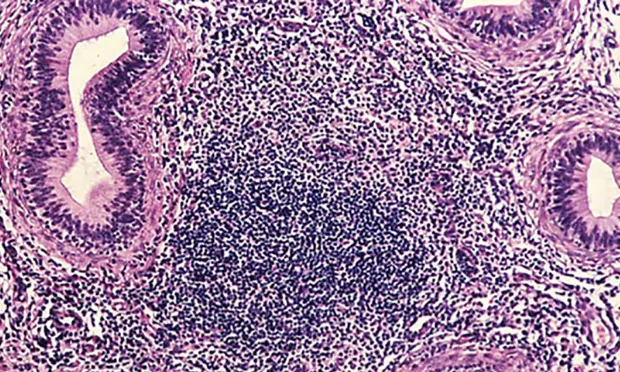

Enzyme-linked immunosorbent assay (ELISA) revealed a positive brucellosis status (Brucella canis infection), which was confirmed with agar gel immunodiffusion (AGID) testing. Qualitative semen culture was performed, and numerous B canis organisms were isolated along with moderate numbers of beta-hemolytic streptococci. The presence of white blood cells in semen cytology suggested a diagnosis of epididymitis. Histopathology demonstrates diffuse lymphocytic inflammation (Figure 2).

Figure 2

Prominent, diffuse lymphocytic inflammation commonly associated with B canis epididymitis. Images courtesy of Cornell Pathology Laboratory